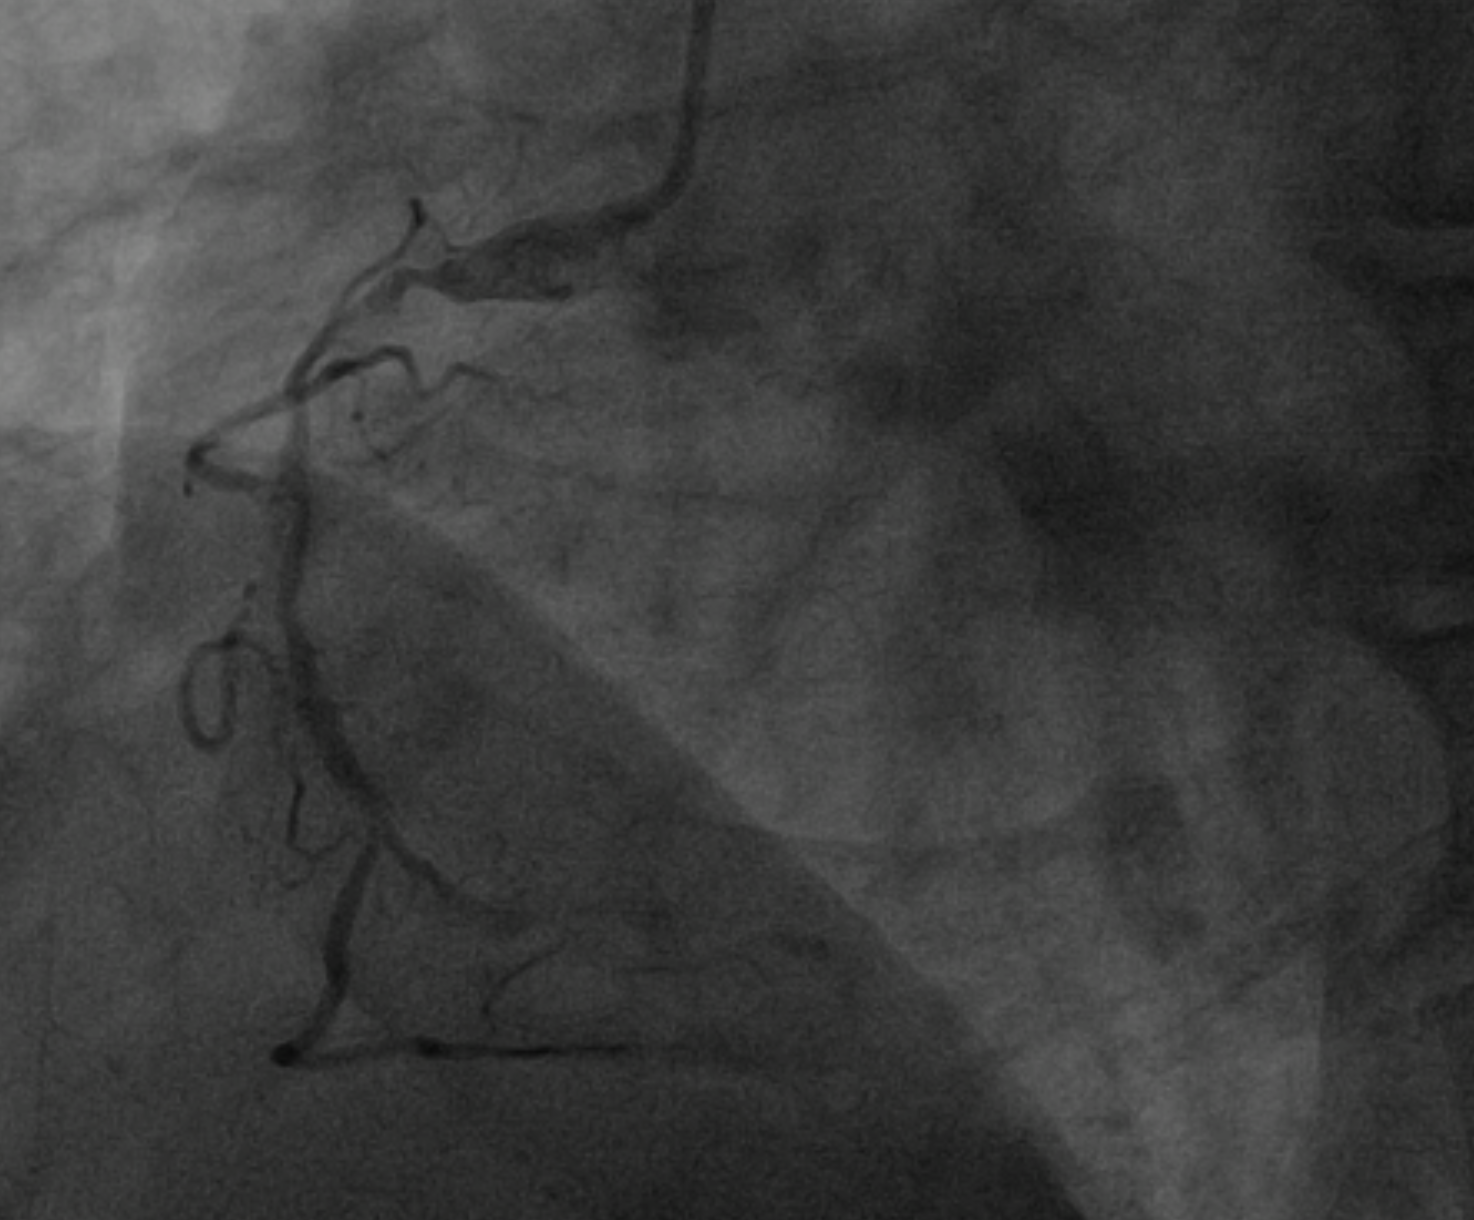

Dominant right coronary artery (RCA) with a heavily calcified, diffusely diseased segment extending from the ostium to the distal portion. The left anterior descending (LAD) and left circumflex (LCx) arteries show irregular but non-significant stenoses

PCI to RCA : Canulation using guiding catheter AL 0.75/7Fr, heparin was administered. Workhorse wire to distal PL. Initial attempt with a 1.5 ¡¿ 15 mm balloon failed to cross the distal lesion and subsequently ruptured. Rotational atherectomy was performed using a 1.5 mm burr at 160–180k rpm with three runs and one polishing pass. A 2.0 ¡¿ 15 mm semi-compliant balloon was then advanced from distal to proximal segments with the assistance of a guide extension catheter.IVUS evaluation demonstrated a 360¡Æ circumferential calcium arc and multiple calcium nodules extending from proximal to distal RCA. Lesion preparation was continued using sequential scoring balloon 2.0 mm and NC 2.5 mm, and cutting balloon 3.0 mm at high pressure. A ¡°dogbone¡± appearance was noted with the cutting balloon at the proximal RCA. An intravascular lithotripsy (IVL) balloon 3.0 mm was then applied to both distal and proximal RCA, delivering a total of 120 pulses (up to 8 atm).Repeat IVUS confirmed adequate calcium modification and optimal lesion preparation. Three overlapping drug-eluting stents (DES) were deployed: 3.0 ¡¿ 38 mm (distal–mid RCA), 3.5 ¡¿ 32 mm (mid RCA), and 4.0 ¡¿ 22 mm (ostial–proximal RCA), followed by sequential post-dilatation up to 4.0 mm. Final IVUS confirmed good stent apposition and expansion, with a minimal stent area of 6.36 mm©÷ at the distal RCA. TIMI 3 flow was achieved. Total contrast volume: 160 mL, Fluoroscopy time: 01:09:34 minutes, DAP: 232 Gy¡¤cm©÷